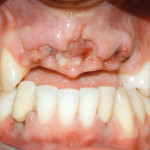

Ricostruzione tridimensionale di un grave difetto mediante rigenerazione ossea guidata (GBR)

Riassunto

La riabilitazione protesica dei pazienti con edentulia totale o parziale mediante impianti dentali è divenuta negli ultimi decenni una pratica comune con ottimi risultati...